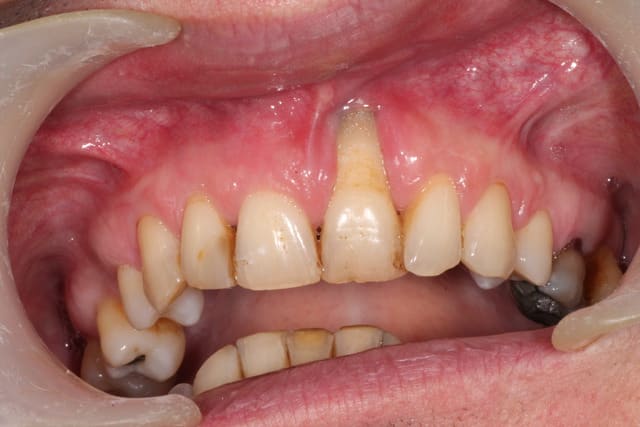

On vois sur le scan l'usure de la face palatine des centrales à cause de la supra. (Donc bridge colle impossible )

Pour moi la bouche est dysfonctionnelle. Évidente supraclusion mais pas seulement.

La déviation de la mandibule à gauche signe une mastication unilatérale à gauche. Si tu as une pano on verra le condyle gauche plus volumineux. Ce qui explique pourquoi 21 et pas 11.

L'usure de 41 est quand même remarquable, non? Quand je vois cette bouche je l'imagine en mouvement: d'abord contact 21 avec inc mand, surtout 41, puis glissement jusqu'à l'OIM. Et elle a fonctionné comme ça toute sa vie.

quelques nouvelles photos :